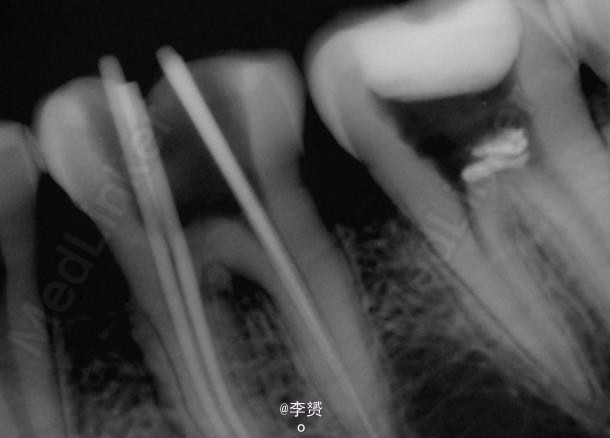

在显微镜下进行断针取出